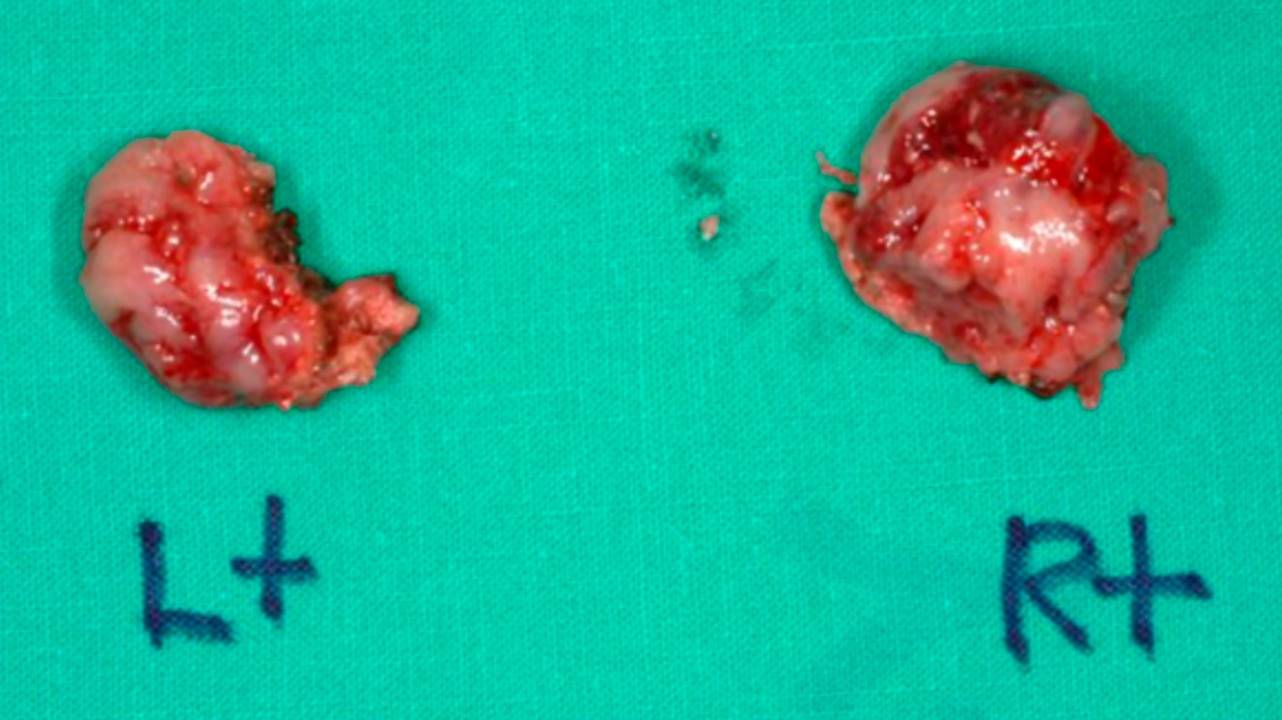

Удаленные миндалины. Maxillofacial Plastic and Reconstructive Surgery / Open-i (Attribution 4.0 International)